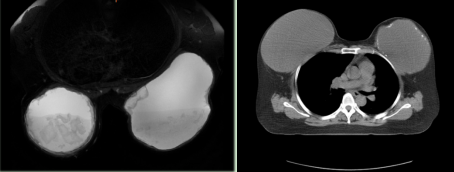

乳房假體CT圖

患者王女士,自述乳房假體置入已有30多年,現(xiàn)在假體位置已經(jīng)處于大幅度偏移狀態(tài)、雙側(cè)乳房不對(duì)稱、影響形體美,同時(shí)局部發(fā)生炎癥、皮膚大面積紅腫,對(duì)其生活產(chǎn)生極大困擾,所以產(chǎn)生了想把假體取出的強(qiáng)烈意愿。2月1日,王女士來我院就診,入甲狀腺乳腺外科住院治療。

患者入院后,經(jīng)過周密的術(shù)前檢查,確認(rèn)王女士符合手術(shù)指征。經(jīng)與患者及家屬溝通,決定為王女士行腔鏡輔助下雙側(cè)乳房假體取出術(shù)。覃勇副主任醫(yī)師表示,腔鏡輔助下乳房假體取出術(shù)與傳統(tǒng)手術(shù)相比具有許多優(yōu)點(diǎn),包括切口更小、創(chuàng)傷更小、術(shù)后恢復(fù)更快。2月5日,甲狀腺乳腺外科團(tuán)隊(duì)成功為患者在腔鏡下取出置入了乳房30多年的假體,手術(shù)十分順利,患者術(shù)后恢復(fù)良好,對(duì)手術(shù)效果非常滿意。